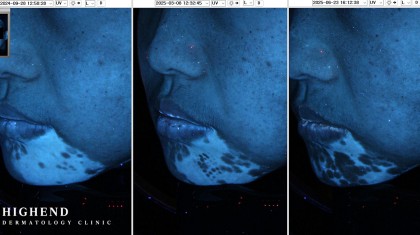

군집성 흑자 치료 사례를 보여드리고자 합니다. 30대 중반의 여성 분으로 입가 양쪽에 군집성 흑자가 나타났습니다.